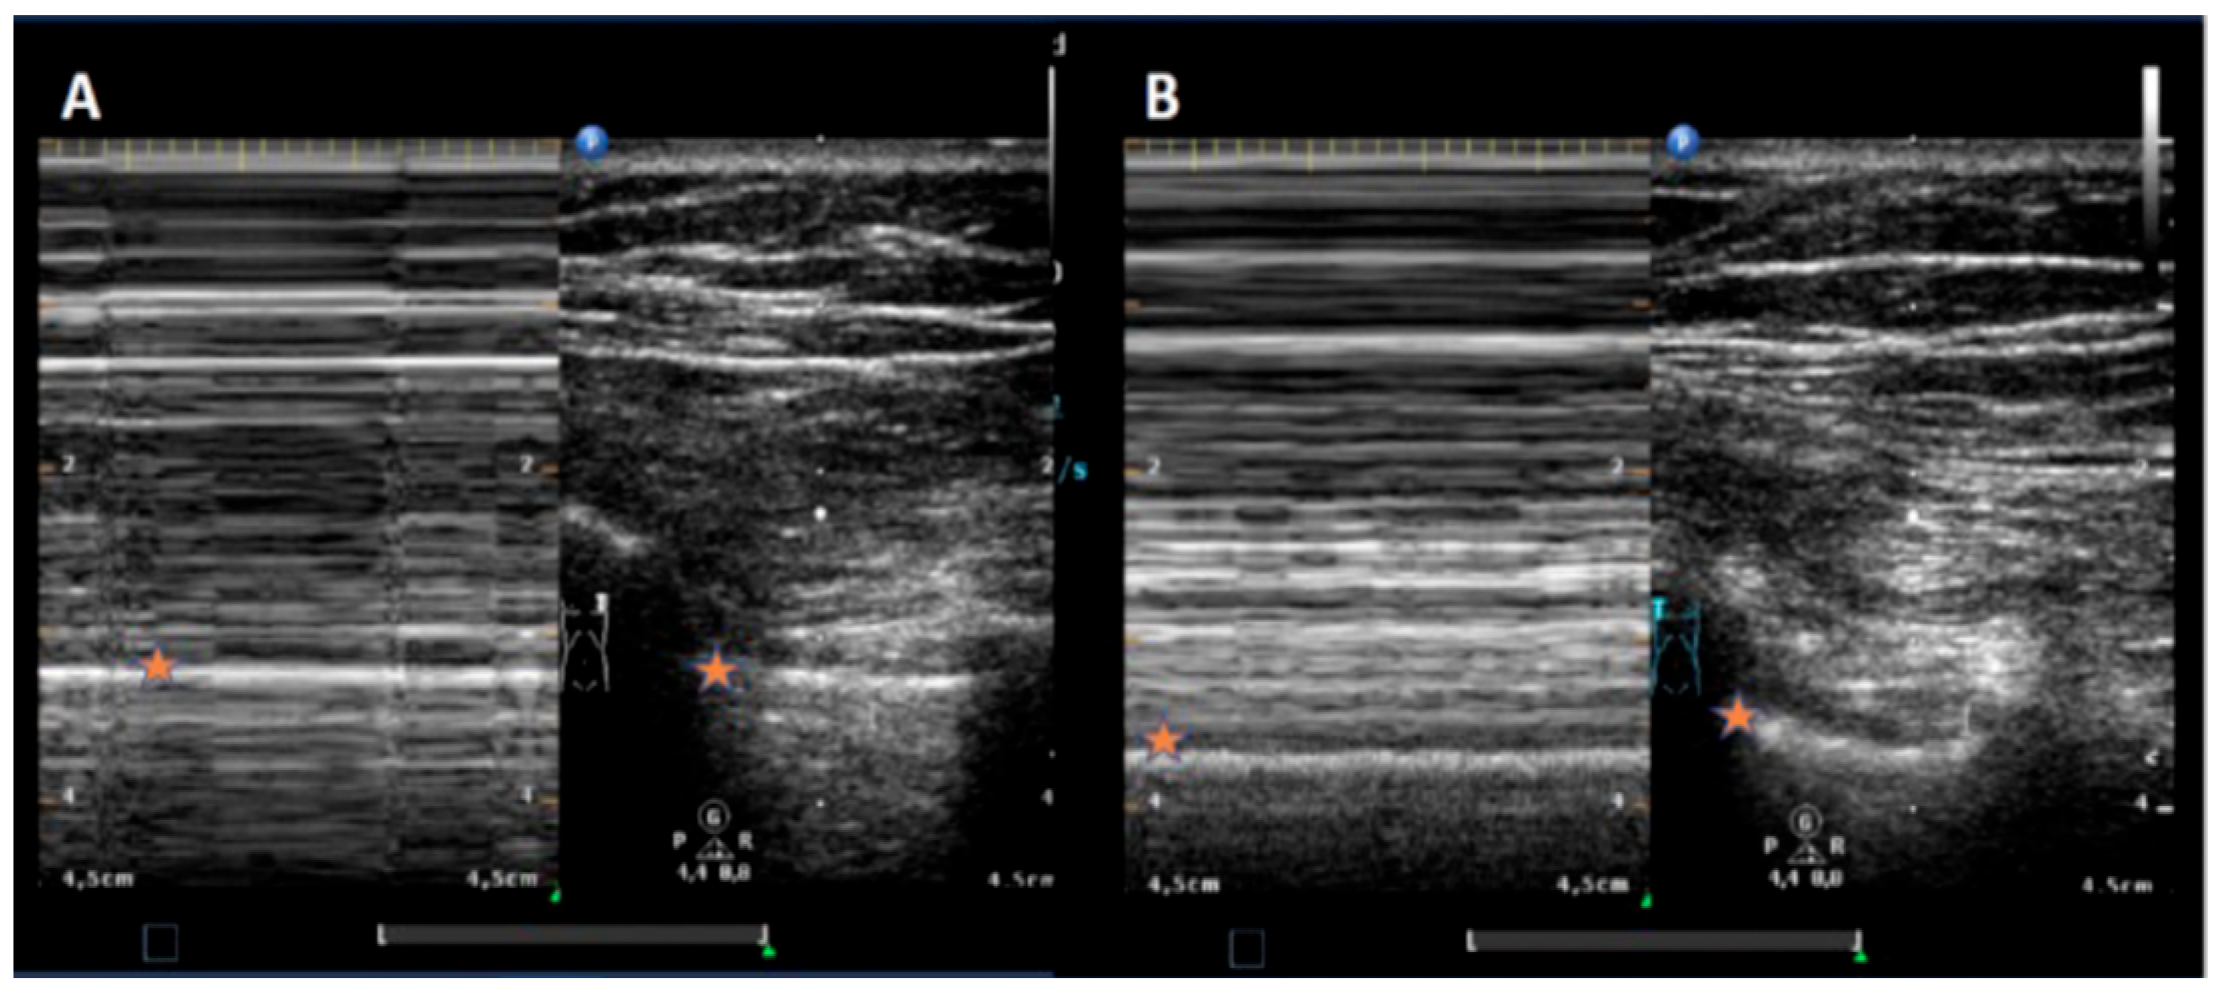

2. Materials and Methods

4. Discussion